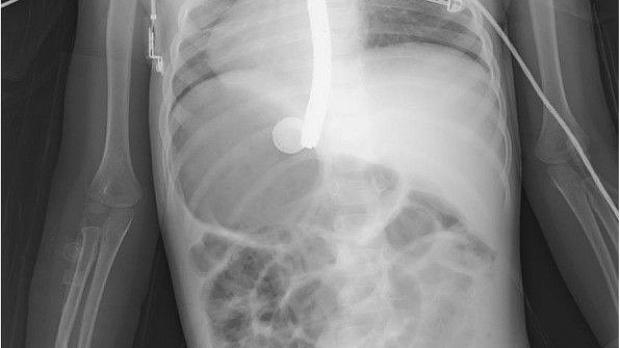

После установки стента в аорту (Advanta™ V12; Atrium Medical Corporation, США; рис. 4) кровотечение было остановлено, достигнута стабильность гемодинамики. Дополнительно проведен эндоскопический гемостаз (Hemospray®; Cook Medical, Ireland). При дальнейших обследованиях рецидива кровотечения не отмечено.

Рисунок 4 [1].